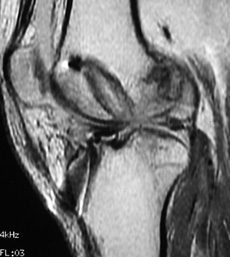

En todos los pacientes de ésta muestra fueron evaluadas radiografías y RMI para determinar las causas de la falla, dividiéndo a los pacientes en 2 grupos en virtud de si las cirugía primaria había sido efectuada por nuestro grupo de trabajo ó por otro. La causa más frecuente de fracaso en nuestra muestra fue el error técnico (75,8%), correspondiendo sólo el 46,8% a un túnel femoral anterior y el 28,5% a un túnel tibial posterior. (Figs.1, 2 y 3)

Figura 2: RMI Corte sagital. Combinación de túneles femoral y tibial anteriores. |

No necesariamente debemos ver el ligamento roto en el estudio complementario, muchas veces nos encontramos con pacientes que consultan por inestabilidad con imágenes de RMI de un ligamento contínuo, pero está este neoligamento cumpliendo verdaderamente su función?

A manera de ejemplo podríamos tomar el túnel tibial posterior, un error técnico que ha aparecido en el 28,5% de nuestra muestra y que nos presenta una imagen homogénea, contínua del neoligamento en la RMI pero con un paciente que manifiesta que en flexión presenta inestabilidad subjetiva. Este paciente presentará una maniobra de Lachman negativa, con tope firme pero también presentará una maniobra de pivot shift francamente positiva y debemos interpretarlo también como un fracaso quirúrgico. (7)

Lo mismo ocurre con las imágenes de RMI. No todos los neoligamentos que se visualizan en las imágenes de RMI con señal homogénea se corresponden con rodillas estables así como también no todas las imágenes de neoligamentos heterogéneos y con alteración de la señal se corresponden con rodillas inestables. (7, 27)